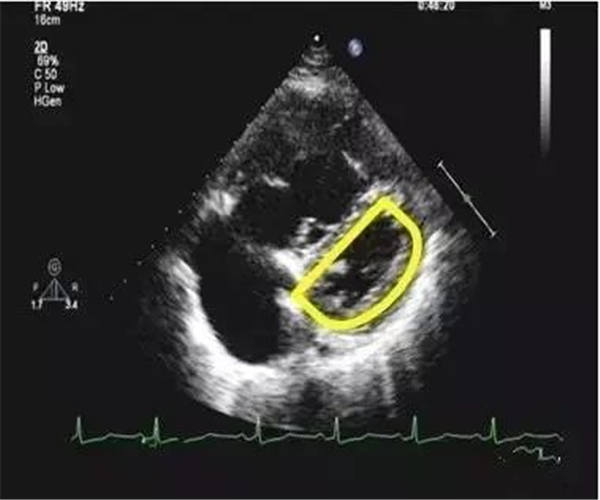

室間隔運動異常

主要表現為左室短軸切面“D”型改變。此時,室間隔偏向左室側,運動平直,收縮期運動幅度減低,與右室前壁及左室后壁運動不同步。